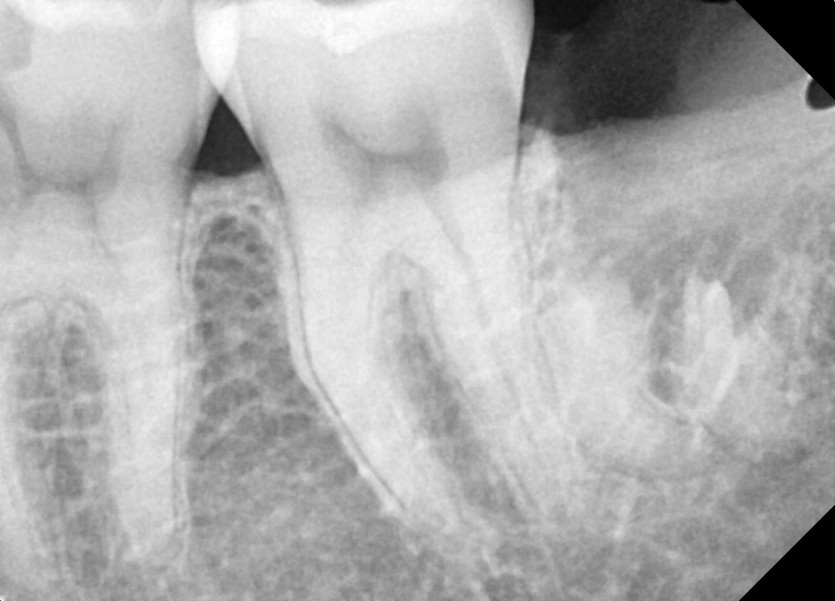

#28,38 사랑니 발치

구강 외과 전문의가 당일 발치했습니다.